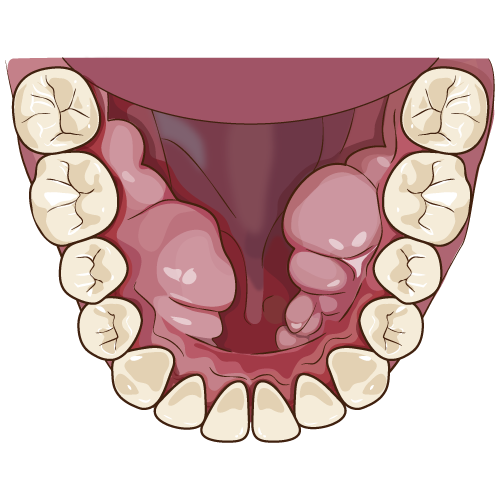

セラミック矯正とは、ご自身の歯を一回り小さく削り上から被せ物を行うことにより、

きれいな歯並びを実現する審美歯科治療のひとつです。

矯正と名前はついていますが、どちらかというと一般的な矯正とは異なり歯自体を動かしたりしないため短い期間で治療を終えられるという特徴があります。

矯正はワイヤーやマウスピースを用いて歯や顎を理想的な位置に動かし、綺麗な見た目とかみ合わせを目的とする治療に対し

セラミック矯正は歯自体の位置は変えないため理想的なかみ合わせよりも見た目の綺麗さに重点を置いた治療になるケースが多いです。